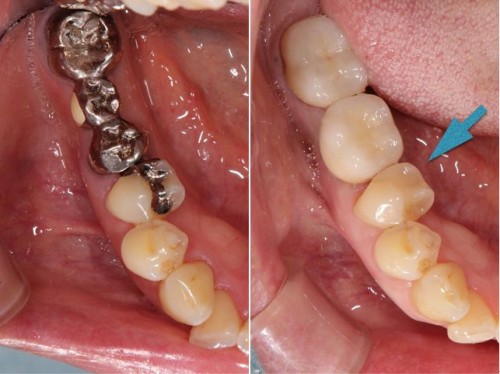

術前術後です。奥歯の銀歯が気になるとの患者様でしたが、このようにセラミックインレーに変更しましたが、大変喜ばれました。